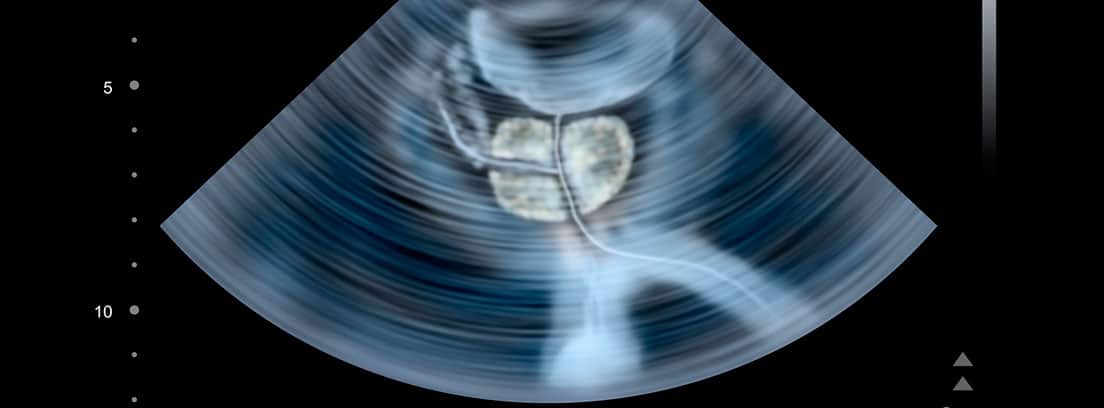

La imagen de una ecografía surge de la aplicación de ecógrafo sobre la zona anatómica a estudio.El ecógrafo emite ondas de ultrasonido que al rebotar sobre el tejido objeto del estudio emite una imagen ecográfica que será recogida en un monitor conectado el ecógrafo. Las imágenes ecográficas obtenidas quedarán recogidas en la pantalla del monitor, en un papel fotográfico o en un CD.

- Ecografía vesico-prostática

- En la ecografía prostática puede ser necesario introducir el ecógrafo cubierto con un aislante de látex a través del esfínter anal (ecografía transrectal) para una mejor visualización de la zona a estudio.

La ecografía vesico-prostática y abdominal se realiza para descartar patologías de vejiga y próstata o determinar la extensión, tipo y tamaño de las posibles lesiones y así realizar un diagnóstico adecuado para proceder al tratamiento que necesite el paciente.